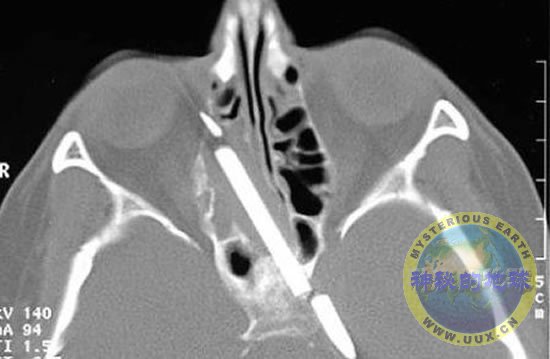

8月,玛格丽特-华格纳接受手术移除了插进头部长达55年的一支铅笔。事故发生在她4岁时,手里拿着铅笔的她不小心摔了一跤,铅笔插进了头部,从那以后,这位德国妇女一直遭受着慢性头痛和鼻出血的折磨。她说:“这支铅笔正好穿过我的头皮消失在我的脑袋里。”当时,因为风险太大,所以没敢做开脑手术移除这支长3英寸的铅笔。幸运的是,这支铅笔没有刺穿脑部任何重要的部位。不过,随着科学技术的不断发展,今年夏天,柏林的外科医生终于顺利地移除了整支铅笔,除笔端依然牢牢地“长”在华格纳脑内之外。